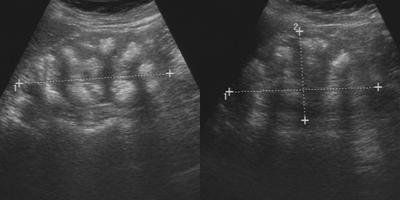

Sonographisch stellten sich die Nieren wie folgt dar: